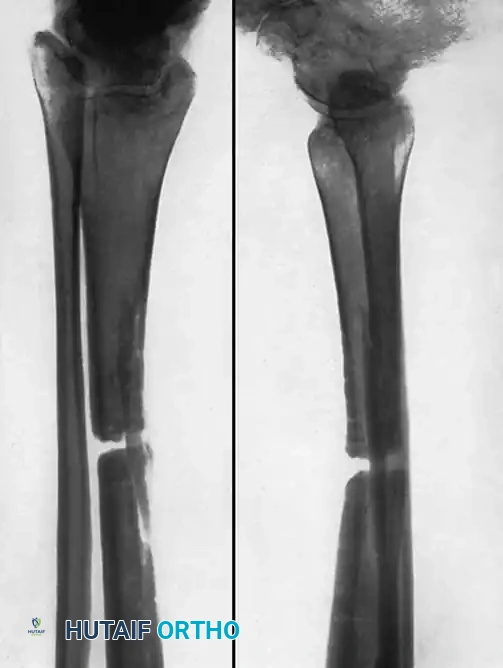

NONUNION OF THE TIBIA

Nonunions are estimated to occur after 2% to 15% of all tibial fractures, making the tibia the most common long bone to experience delayed union or nonunion. The subcutaneous nature of the anteromedial tibial face renders it highly susceptible to high-energy trauma, open fractures, and severe soft-tissue compromise.

TIBIAL SHAFT NONUNIONS

Many treatment methods have been highly successful in obtaining union of tibial shaft nonunions. Union rates of 72.1% to 87.8% have been reported with closed bone grafting procedures in hypertrophic aseptic nonunions. Internal fixation (intramedullary nailing or plating) has been reported to obtain union in up to 98% of cases, and electrical stimulation in 78.8%.

Because the tibia is a primary weight-bearing bone, its length, alignment, and rotation are critical to the biomechanical function of the knee and ankle. Simply obtaining union is insufficient; union must be achieved in an anatomic position to prevent adjacent joint arthrosis.

Hypervascular vs. Avascular Nonunions

The surgical technique selected depends heavily on whether the nonunion is hypervascular (hypertrophic) or avascular (atrophic), and whether the alignment of the fragments is satisfactory.

- Hypervascular Nonunions: The bone ends possess excellent biological capacity to unite but lack mechanical stability. In these cases, rigid internal fixation with a compression plate, an intramedullary nail, or a circular external fixator is usually all that is necessary. Supplemental bone grafting is rarely required.

- Avascular Nonunions: The bone ends are sclerotic, necrotic, and lack osteogenic potential. Rigid internal fixation must be supplemented by aggressive decortication of the sclerotic bone ends (shingling) and the application of autogenous bone graft. Weber and Brunner, Müller and Thomas, and Christensen have found these combined methods highly successful.